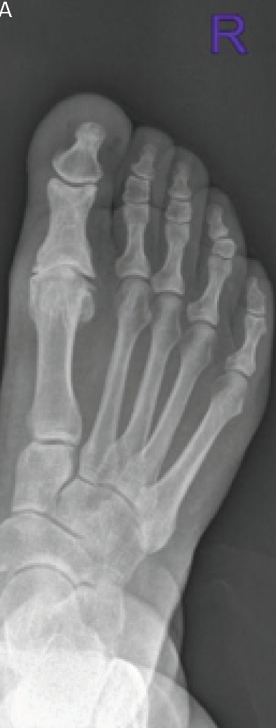

A. Halluks rigidusta eklemdeki bozukluğun görünümü

B. Halluks rigiduslu hastanın röntgen filmi